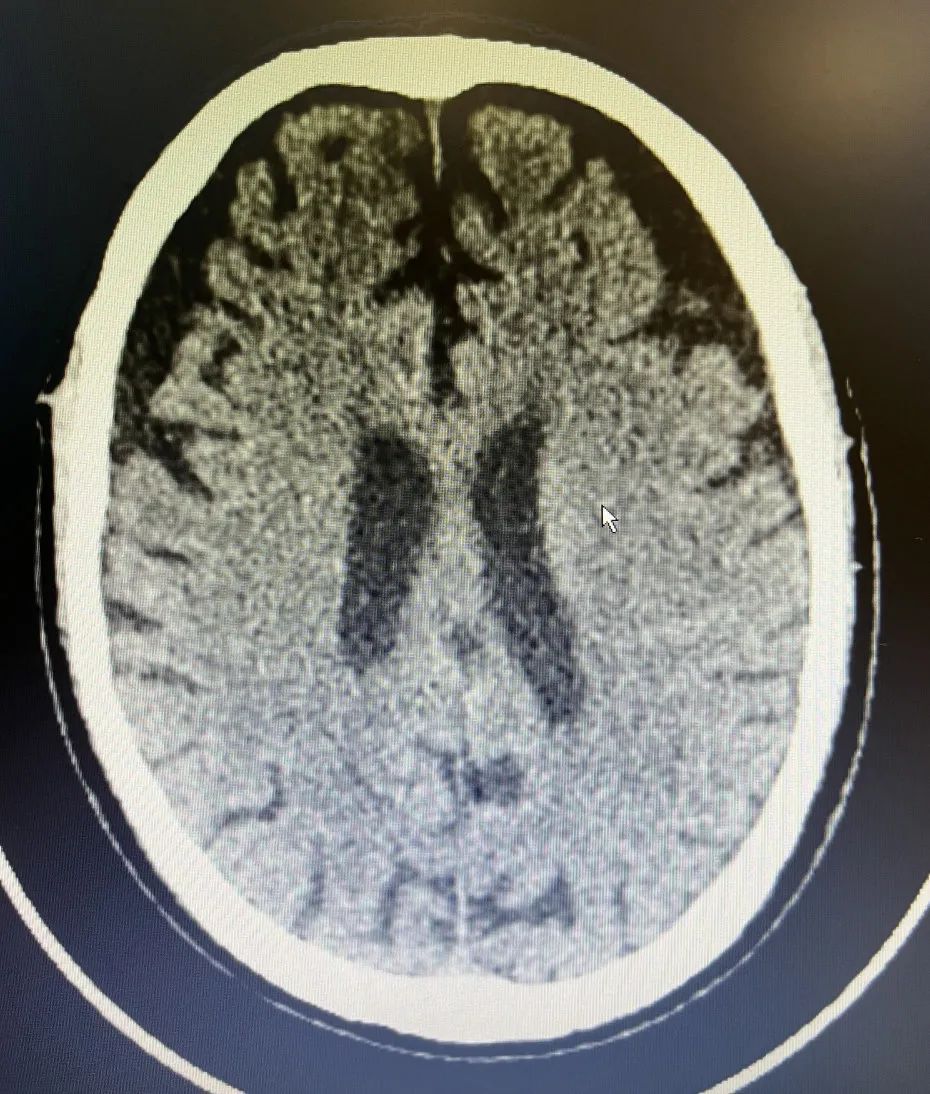

1. 左侧额顶颞枕部慢性硬膜下血肿伴大脑镰下疝形成。

2. 右侧额顶部硬膜下血肿

来不及半分耽误,神经疾病科副主任医师叶信珍亲自操刀进行手术,带领团队顺利清除部分血肿,并且保留引流管持续引流。术后蒋爷爷安返病房。